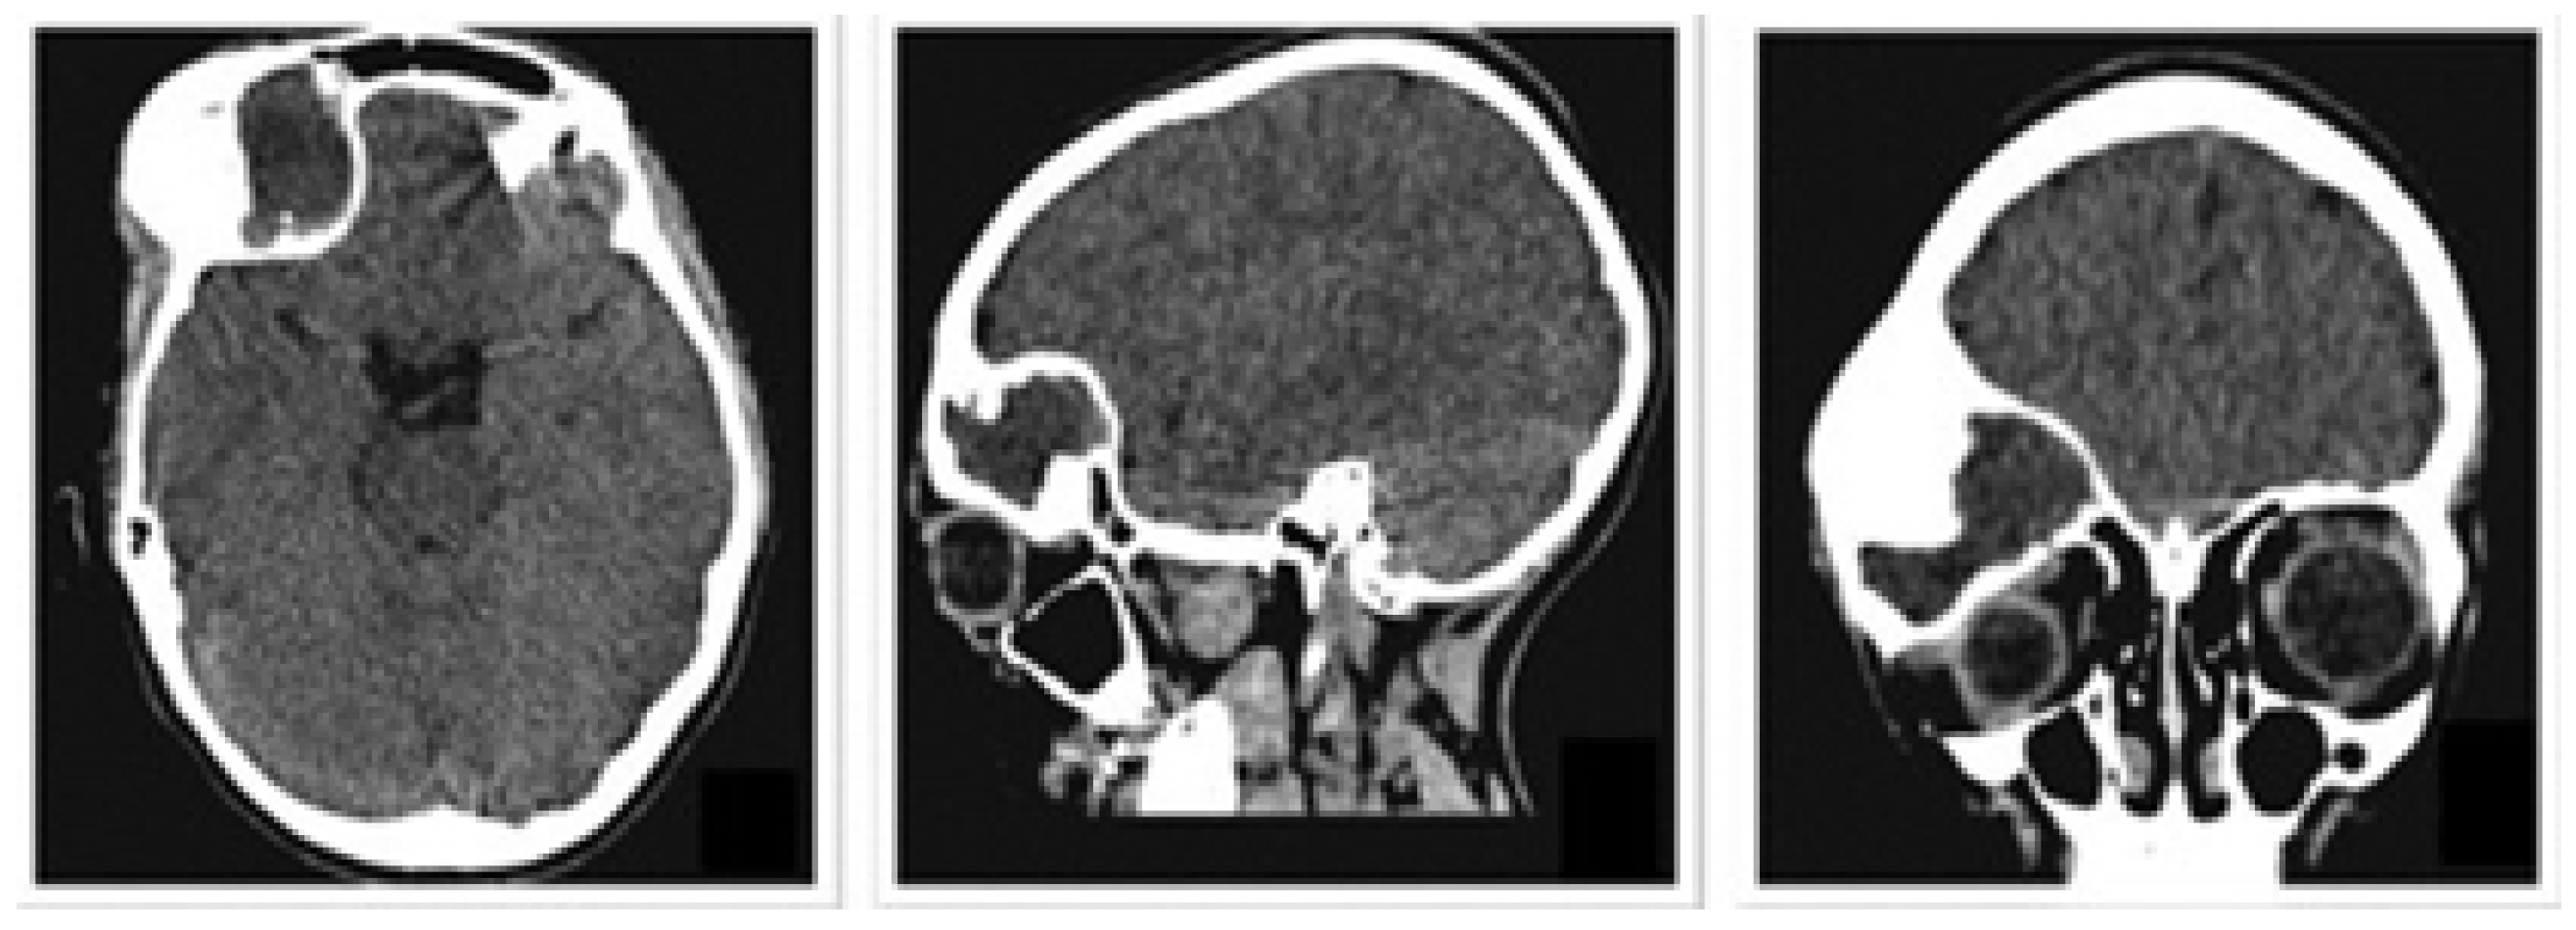

A 9-month-old female patient presented with metopic craniosynostosis and trigonocephaly, characterised by premature fusion of the metopic suture, resulting in a triangular frontal deformity and possible hypertelorism. The recommended treatment in this situation is cranial remodelling surgery. Figure 43 shows different aspects of defect identification using tomographic images.

Figure 43. Different aspects of deformity identification (tomographic image).